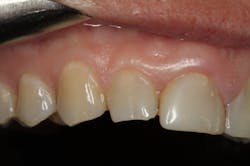

We digitally analyze our esthetics and smile design using the Dawson Diagnostic Wizard (the Dawson Academy). One of our biggest esthetic concerns in this case was caused by a functional issue. As you can see in the photos (figures 1 and 2), the patient has significantly more attritional wear on the right side versus the left. Due to the wear, the right anterior teeth have suffered from more compensatory eruption than the left, which results in uneven gingival architecture and esthetically displeasing length-to-width ratios of the anterior teeth (figures 3 and 4).

When we start to look at our occlusal shots (figures 5 and 6), it is obvious that we have some acidic erosion into dentin as well as significant wear facets from attrition. The pulp chambers of teeth Nos. 8 and 9 are now visible due to the loss of lingual tooth structure.